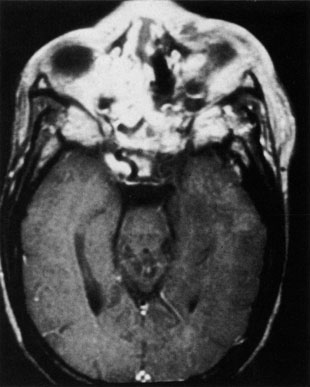

MRI is superior to CT in the diagnosis of cavernous sinus thrombosis. T2- and proton-weighted images show high signal luminal narrowing as well as absent flow or localized parenchymal infarcts (Fig. 20).72 Absent flow can be demonstrated as well in the superior ophthalmic vein in cases of carotid or cavernous sinus thrombosis.72 MRI with gadolinium can help define these abnormalities and can detect dural invasion.

Fig. 20. Cavernous sinus thrombosis. Axial T1 image shows cavernous carotid luminal narrowing on right and enlargement of right cavernous sinus. Note extensive sinus disease.